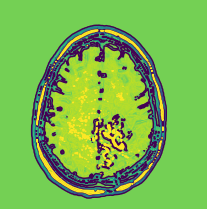

Refer to caption

(a) Malignant GS

(b) Malignant CT

(c) Malignant SE

(d) Malignant SD

Figure 12: Proposed preprocessing applied over malignant MRI images.

Figure-12 shows a transition of the various stages of the proposed preprocessing for a malignant brain neoplasm. The contour of the malignant brain produces a centralized yellow region as seen in Fig. 12(b). But when compared with the difference contour, the less interesting regions are colored green with a brown border as previously seen with benign MRI. Further, a brown edge with yellow is is seen in the final image where the malignant neoplasm is present as seen in Fig. 12(d). The proposed preprocessing can outline the portion with the brain tumor effectively, even if the tumor is discreetly spaced. Further, many preprocessing techniques tend to over soften the image during the noise removal process to get better accuracy, but this changes the original image features. This proves to be beneficial when detecting the presence of neoplasm but during the classification of the severity, this process fails to get good results. But in the case of the proposed preprocessing, the final output MRI image is free of over softness and hence the features are preserved better.